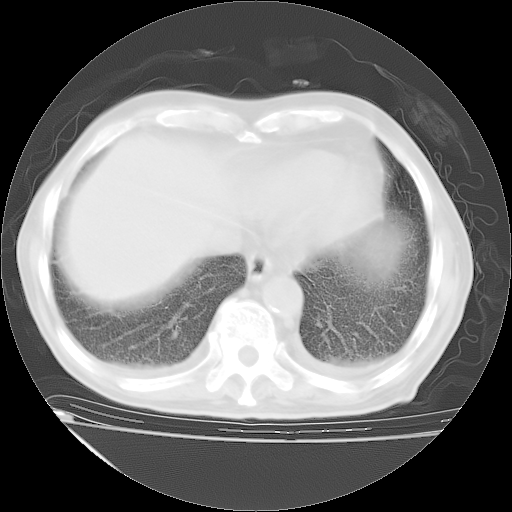

甲强龙80mg/日+抗结核治疗(异烟肼+利福霉素+乙胺丁醇)10天。复查肺部CT。

治疗10天肺部CT